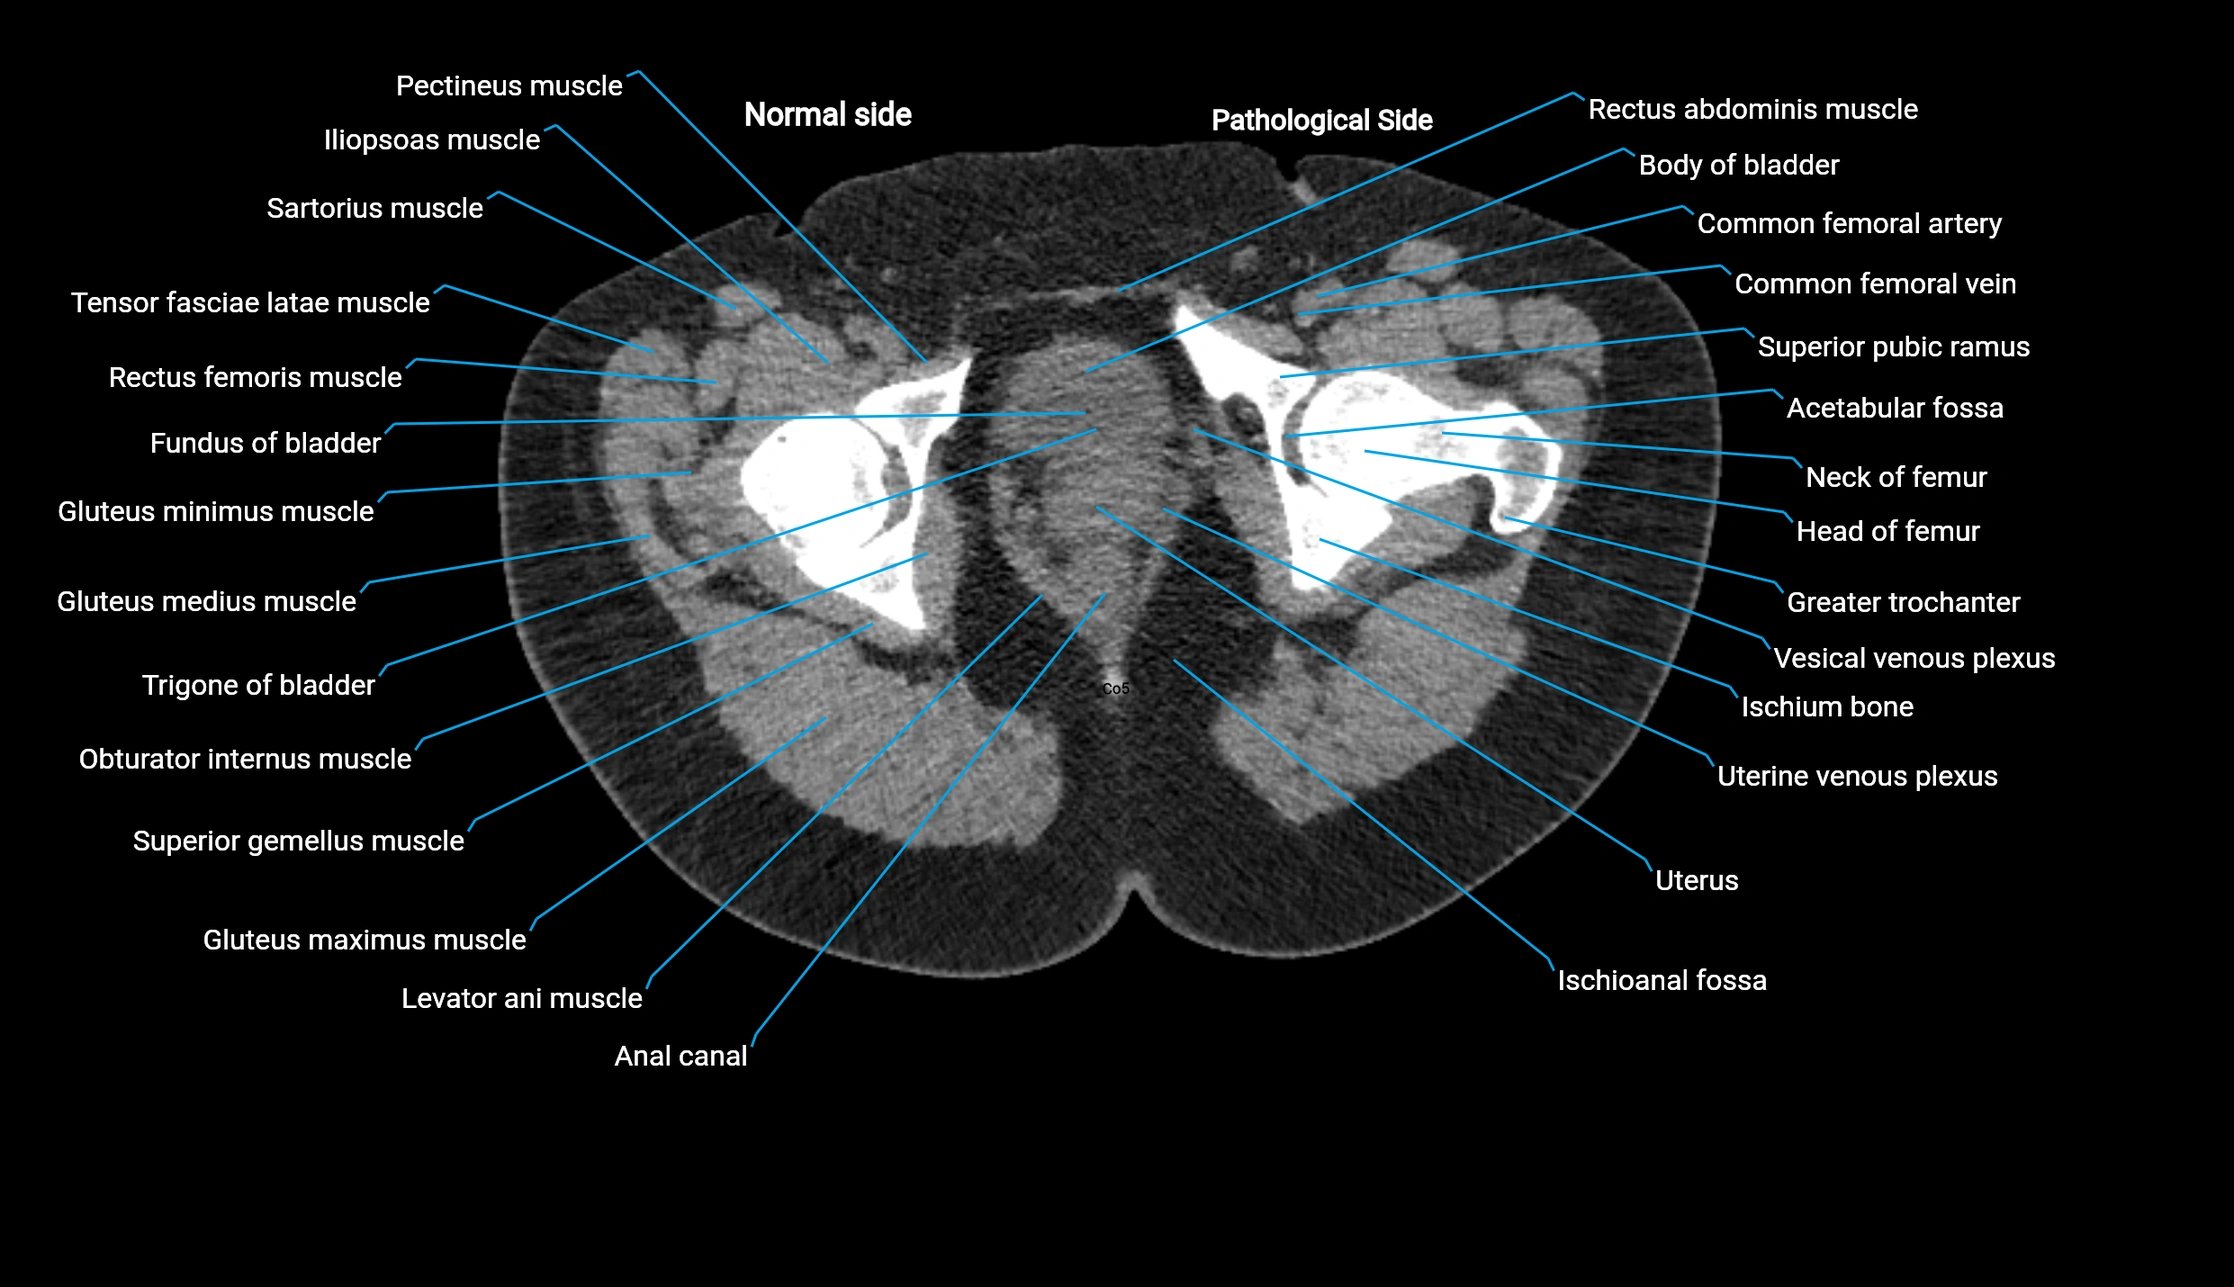

CT image

image